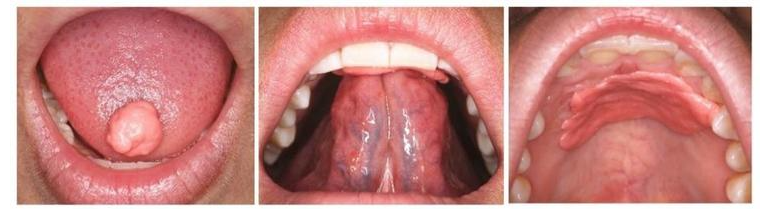

舌头的正常位置应该是上牙膛往上,当你闭嘴的时候,舌尖应该是顶着你上面牙的舌面。但是有些人的舌肌位置不对,比如上下牙之间是开的,也就是开颌,那他在说话的时候,你会发现他的舌头像蛇一样从牙之间钻出来;有些人反颌,他的舌头是在下牙,所以下牙会比较突出。

C、弹舌训练:舌体打击上颚动作并发出响声,每组20次,每天3组。若舌系带短小时,可通过手术创造便于舌体上抬的环境